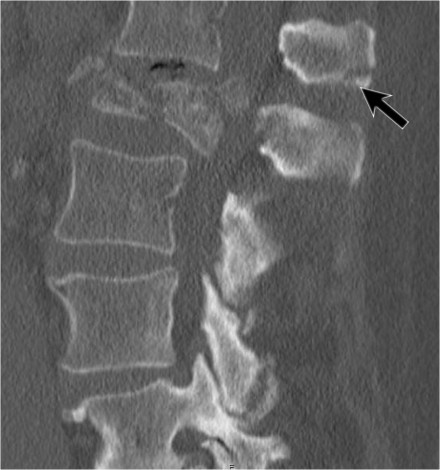

The images are of a patient with a typical bamboo spine as a result of ankylosing spondylitis.

After a fall on his back no fracture was seen on the x-rays.

However the CT shows a thin fracture line through the anterior side of the vertebral body and also through the spinous process.

Continue with the MR-images.